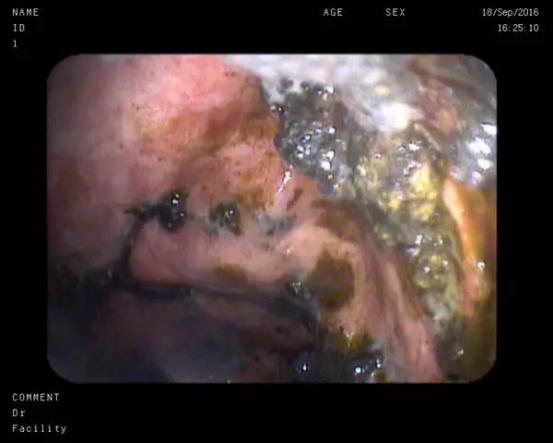

使用鼻胃镜经支架进入囊腔内对坏死物质进行清理

此次患者郑某、耿某均于半年前发生胰腺炎,病情稳定后逐渐出现腹胀、进食后呕吐等梗阻症状,入院后经CT检查发现巨大胰腺假性囊肿形成。我院东院消化内科以张春清主任、张俊勇副主任医师为首的超声内镜介入团队,带领冯华主治医师、王广川主治医师,结合疾病特点和既往经验,反复研究琢磨,借鉴先心病室间隔缺损“封堵器”的原理,创新采用特制双蘑菇头覆膜支架代替传统胆道支架,通过膨大的双蘑菇头将胃壁和囊壁牢牢卡在一起,从而避免支架滑脱的可能,另外宽大的蘑菇头使术者可以轻松的操作鼻胃镜经支架中间孔道进入囊腔,进而对囊内坏死物质进行冲洗和清理,促进患者恢复。两位患者在植入双蘑菇头支架后,腹胀症状迅速缓解,即可正常饮食,经4周引流,复查CT囊肿基本消失,支架无任何移位,遂在内镜下将支架取出,胃壁创口愈合良好。